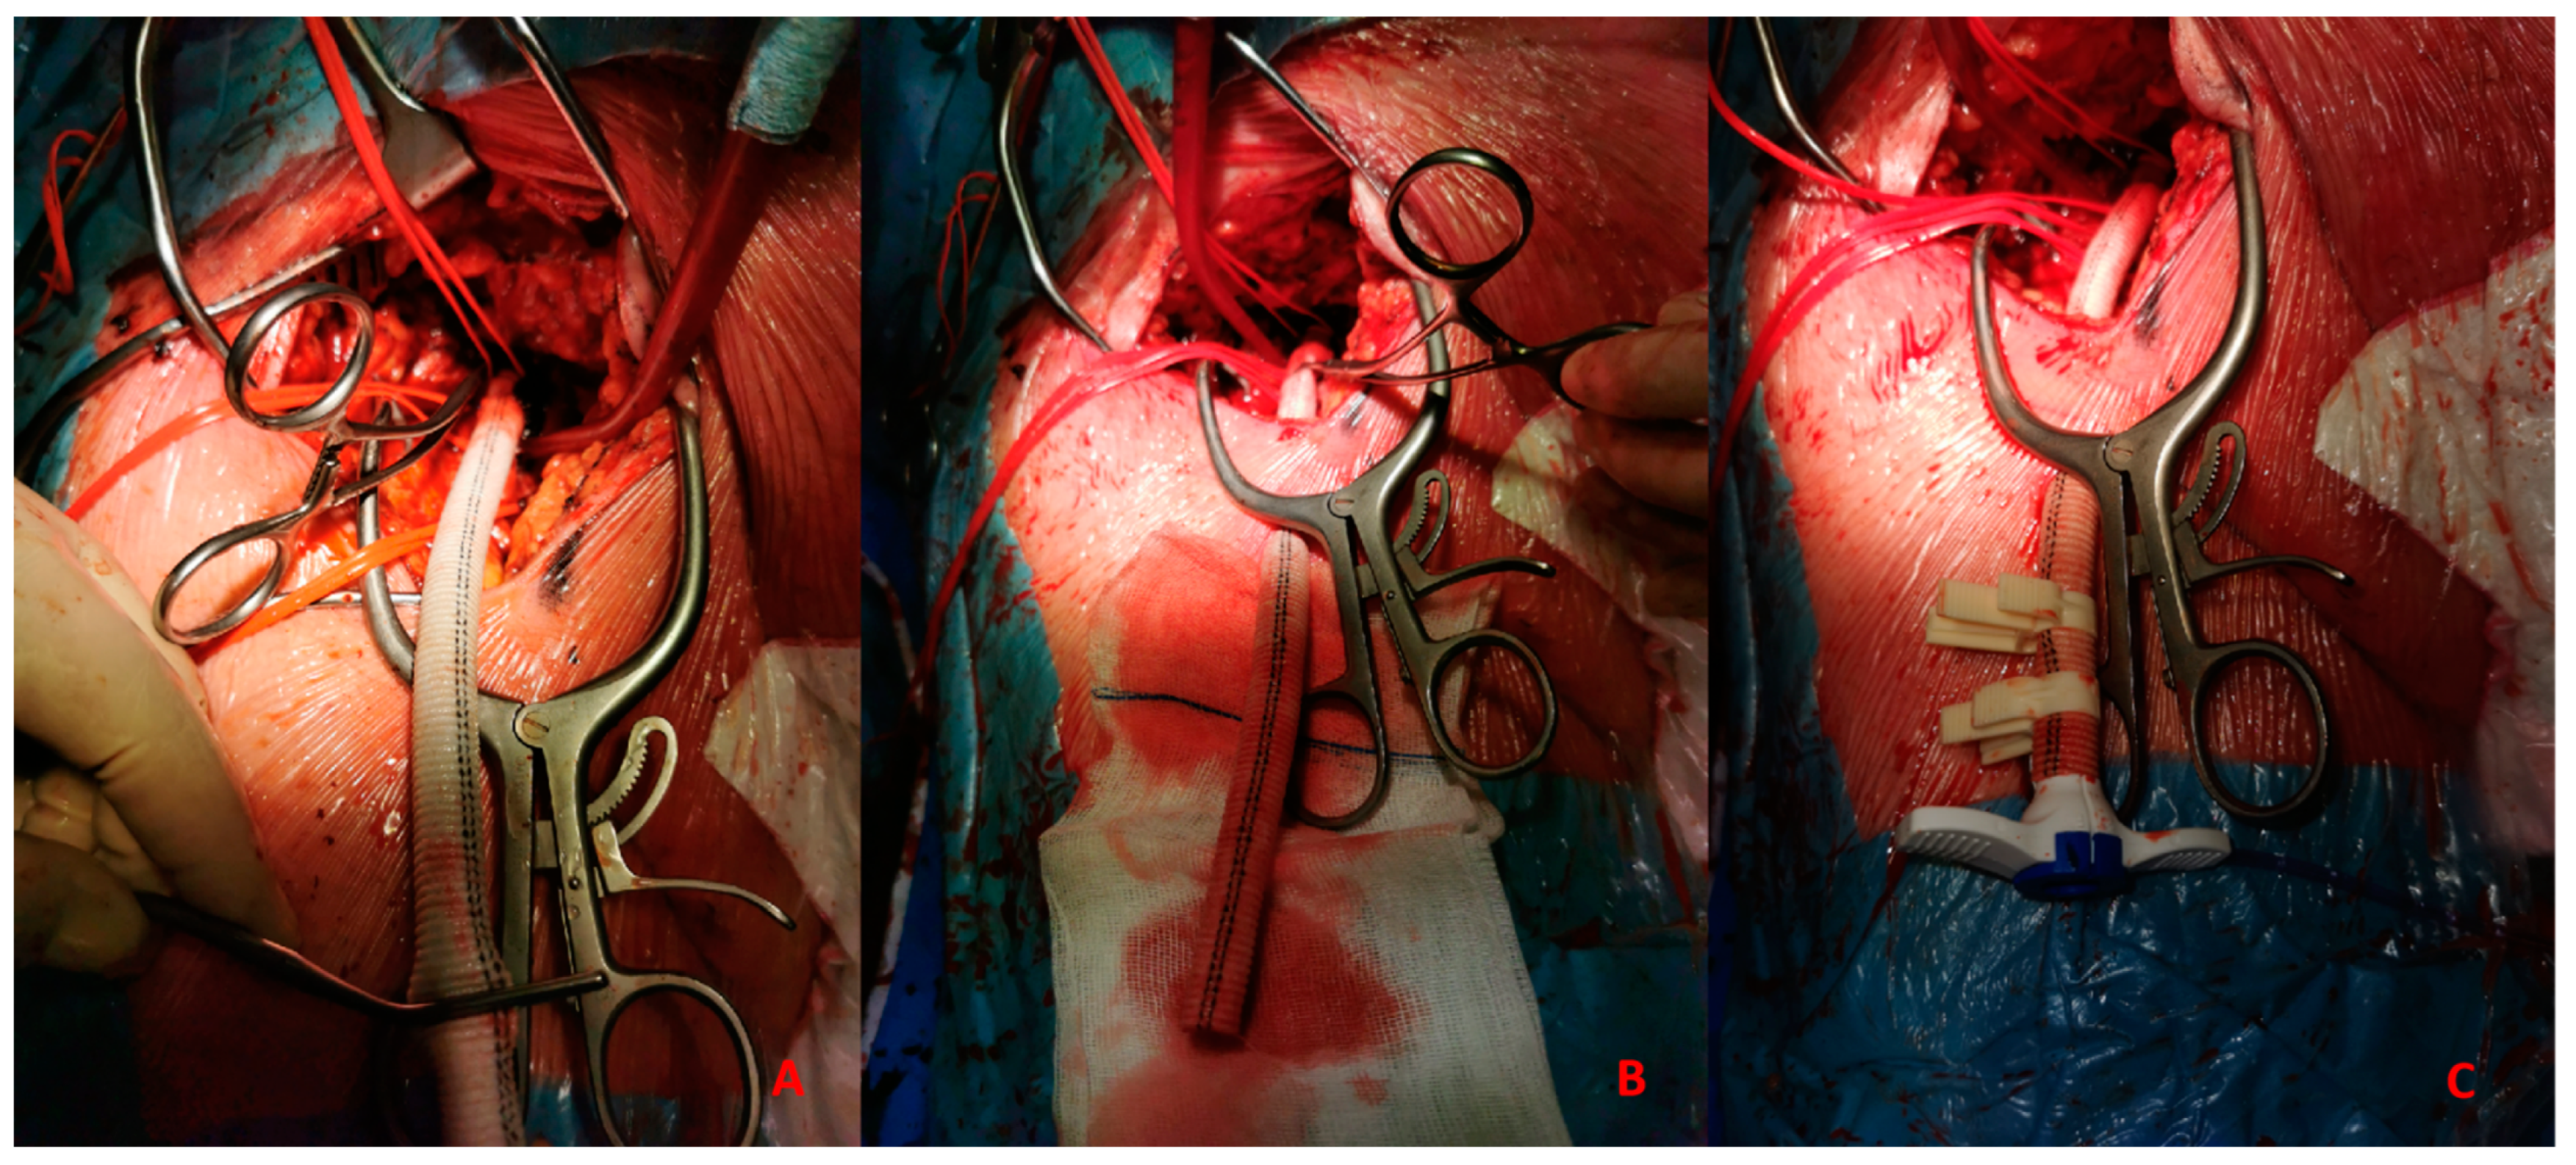

- Surgical: This approach is usually preferred in select cases, such as extremely obese patients. The surgical approach could be performed to expose the artery and the subsequent “de visu” puncture Figure 4. Moreover, a vascular graft can be anastomosed to the CFA with the insertion of a short sheath in the conduit.

Figure 4. (A) 51-year-old man with history of: diabetes, chronic obstructive pulmonary desease (COPD), mild chronic kidney disease (GFR 56 mL/min) and peripheral artery disease (PAD) with previous percutaneous transluminal angioplasty (PTA) with stent implantation in the right external iliac artery, left iliac artery, left common femoral artery and subsequently aorto-bifemoral bypass surgery, referred to our center for HR-PCI A. Angiography evaluation after sheaths insertion. (B) Surgical cutdown with VA-ECMO cannulation and subsequently insertion of 7 Fr guiding sheats.This approach includes six different steps:- -

- Skin incision on the groin Figure 5A

Figure 5. (A). Skin incision on the groin. (B). Exposure of common femoral artery. - -

- Exposure of CFA and the femoral bifurcation Figure 5B

- -

- Arteriotomy of CFA

- Anastomosis between CFA and a vascular graft Figure 6A

Figure 6. (A). Vascular graft and common femoral artery anastomosis. (B). Tunnellization of vascular graft under the skin. (C). Insertion of Impella 5.0 sheath in the vascular graft. - -

- Tunnellization of vascular graft under the groin skin Figure 6B

- Insertion of the sheath inside the vascular graft Figure 6C